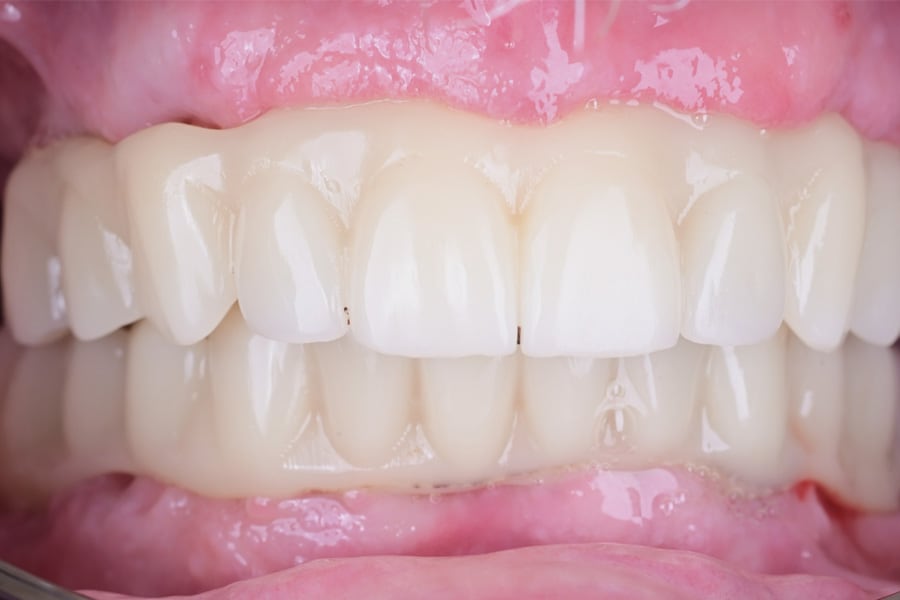

Definitive frameworks were CAD-designed and CNC-milled from titanium alloy (Figure 22). Clinical fit was confirmed with the Sheffield test (Figure 23). Monolithic zirconia superstructures were produced and vestibularly veneered with feldspathic ceramics to enhance translucency and texture (Figure 24 and Figure 25). Selective pink ceramic was applied in gingival areas requiring soft-tissue compensation (Figure 26 and Figure 27).

Occlusion was once again validated using jaw-motion tracking, confirming harmony with functional dynamics (Figure 28). The definitive prostheses were delivered as screw-retained restorations, achieving esthetic integration, functional stability, and patient satisfaction (Figure 29 and Figure 30).